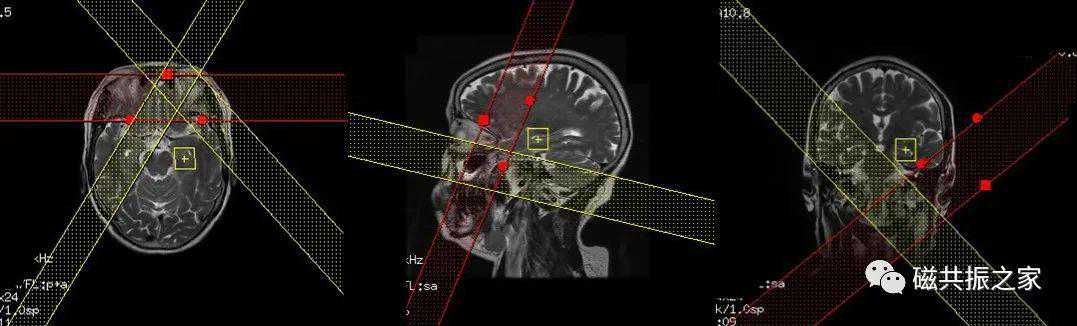

在横轴位和冠状位上定位,在横轴面上找到显示海马结构最好的层面,分别在两侧定位使定位线平行于海马的长轴,在冠状位上调整角度,使两侧分别于两侧颞叶底垂直,范围包括整个海马结构,需包括整个病变范围。

双侧定位线避免交叉产生伪影。

定位的精准和饱和带的合理使用是获得优异谱线的关键。单体素MRS定位时应注意横、矢、冠状位上的定位体素位置的准确性,尽量避开影响谱线质量的组织和区域(如气体,脂肪、骨质、血管等)。

上图△,体素10*20*10。